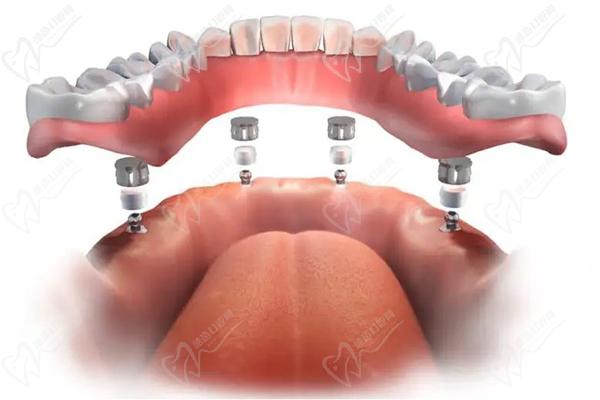

適合于:預(yù)算不高的全口缺牙修復(fù)患者,采用的是桿卡式、球帽式兩種方式固定全口牙。全口半固定種植牙是種植體和活動假牙的結(jié)合,也叫做種植覆蓋義齒,半固定種植牙分為桿卡和球帽式兩種,滿口植入4~8顆種植體,然后再利用緊密部件(桿卡式或球帽式)將烤瓷或全瓷牙冠固定在種植體上,實現(xiàn)全口種植,上面的假牙是可以自行摘帶的,但不容易脫落。

西安滿口半固定種植牙價格:1.8萬-5萬左右